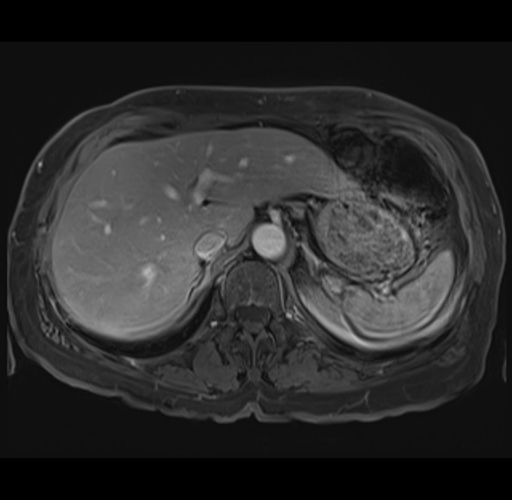

MRI T1

Imaging analysis

Based on your CT findings, which issue(s) would give reason for "planned slowing down moment(s)" in this case?

Considering a standard right hepatectomy procedure, what step(s) of the operation would you do differently in this case?